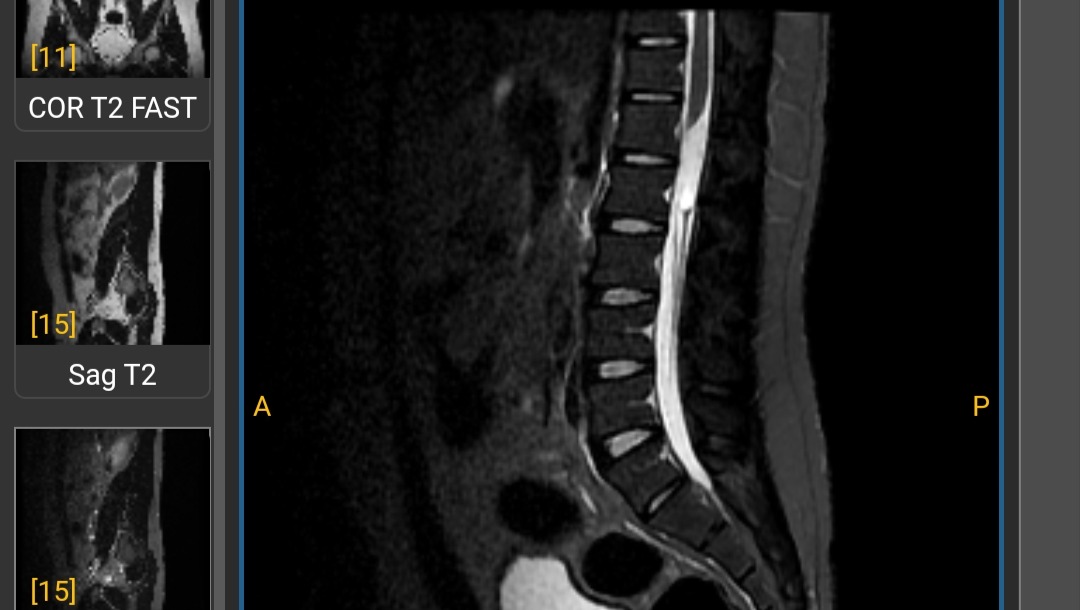

On September 4th of 2023 a tumor of approximately 8-9 CM long was found in the lower section of my spine. This tumor slowly took away my ability to function and do normal day to day activities, couldn't get out of bed, stand up, or walk alone. After multiple appointments and diagnostics from 3 different neurosurgeons, I was urged to have surgery in my spine to have the tumor extracted.

MRI